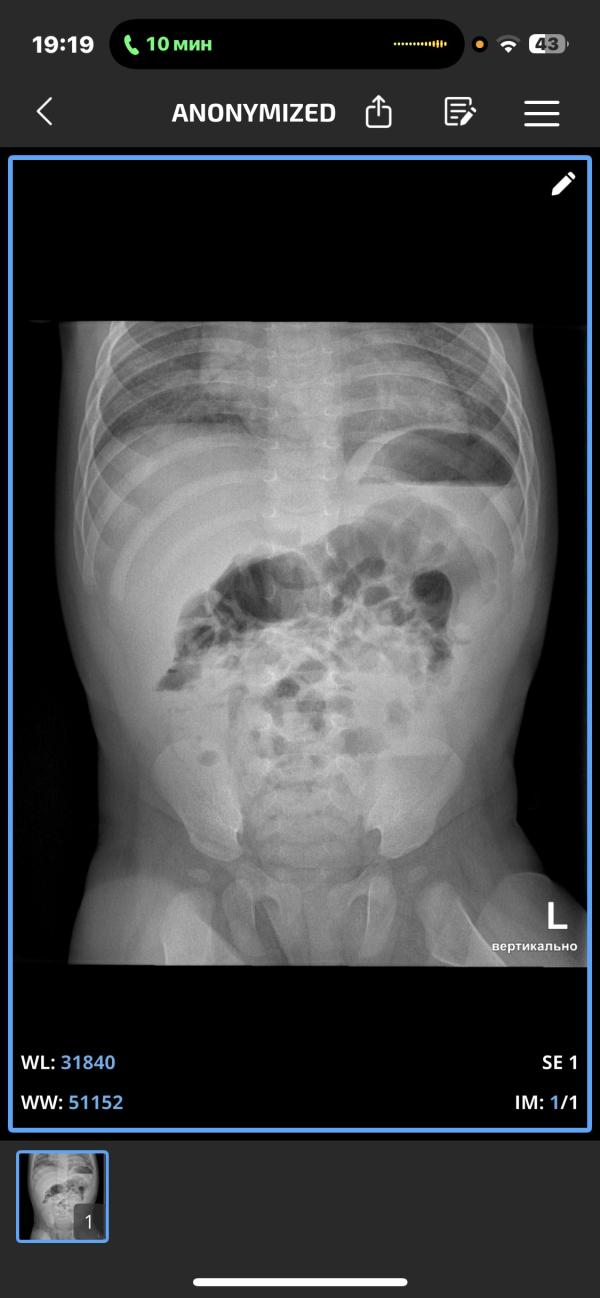

Девочки кто понимает в этих рентгенах сколько там поражено ?? До завтра с ума сойду(( щас сказали у малыша двусторонняя пневмония 😢

@sabrisafi, с реактивный белок не повышен, при бактериальной пневмонии он зашкаливает(

Попросите проверить на микоплазменную пневмонию. У нас когда случилось первый раз, долго не могли поставить диагноз, по рентгену пневмония, но ничего не помогало, потом взяли на микоплазменную и оказалась она, а при ней только один антибиотик помогает.